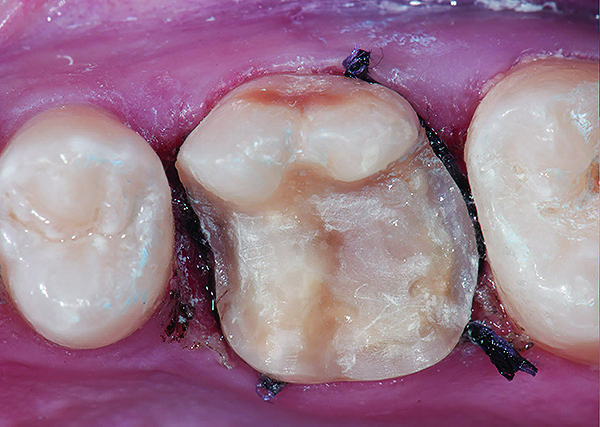

Figure 9 Preoperative preparation with composite block-out restoration, final cementation of Class IIb material, and final ceramic contour and stain by Steve Lee, CDT, MDC.

Figure 9

Figure 10 Preoperative preparation with composite block-out restoration, final cementation of Class IIb material, and final ceramic contour and stain by Steve Lee, CDT, MDC.

Figure 10

Figure 11 Preoperative preparation with composite block-out restoration, final cementation of Class IIb material, and final ceramic contour and stain by Steve Lee, CDT, MDC.

Figure 11